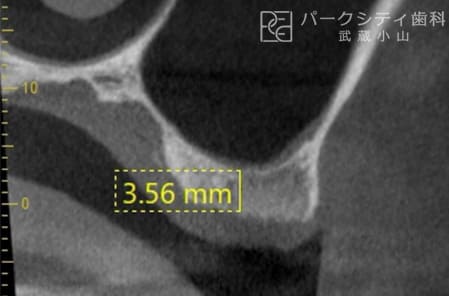

上顎洞挙上術(クレスタルアプローチ)

- 適応症:

上顎の奥歯部分の骨の高さが3~5mm以上ある場合。 - 方法: